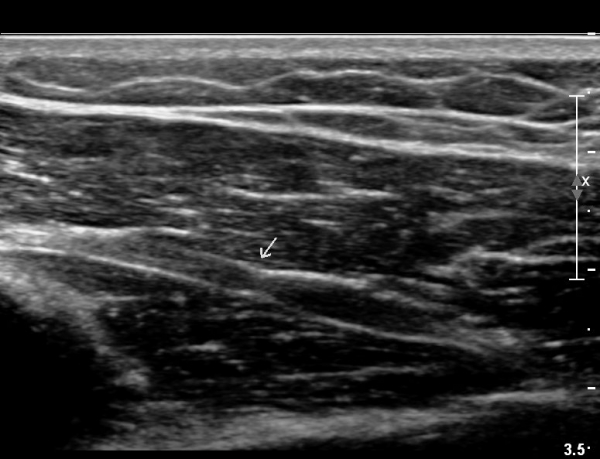

ŽÃÊÀÚ¸¦ Á¶±Ý ´õ ¸»´ÜÀ¸·Î À̵¿ÇÏ´Ï ¿ä°ñ½Å°æÀÌ °üÂûµÇÁö ¾Ê°í(»çÁø3),